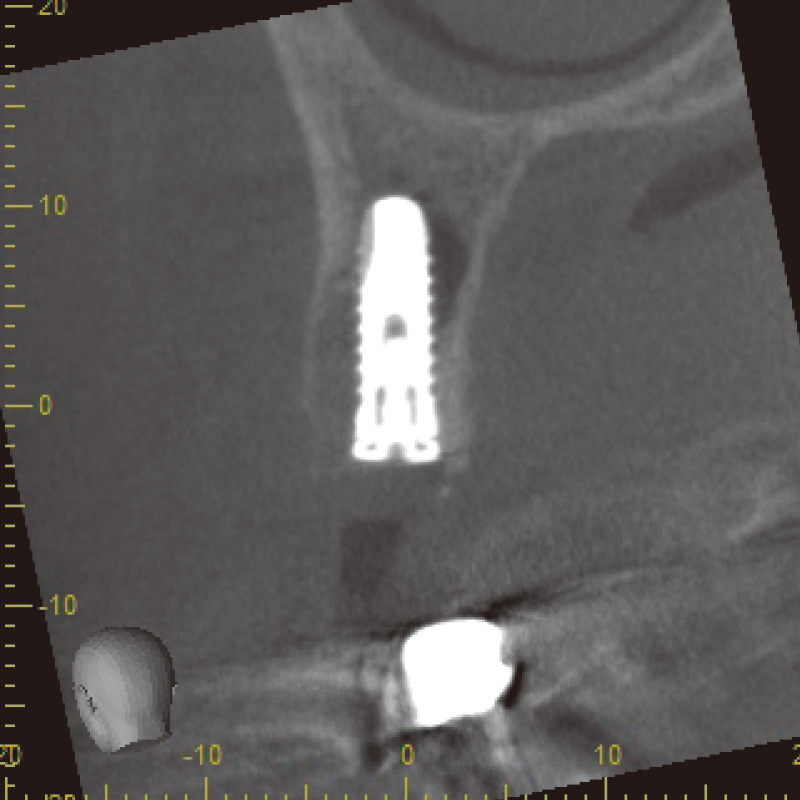

図6 SPIインプラント埋入 CT画像① -

![[写真] CT画像](/academic/dentalmagazine/wp-content/uploads/sites/2/2025/11/195-8_photo07.jpg)

図7 SPIインプラント埋入 CT画像② -

術前診断には、CBCTを使用した。高精度な3D画像診断を行うことができ、骨質、骨量、根尖病巣、破折部位の状況を詳細に評価できるため、即時埋入に必要な治療計画を立てるのに非常に有効であった。特に、根尖部に疑われる破折線や歯根膜腔の拡大が確認され、SPIインプラントを選択し、即時埋入を実施した。